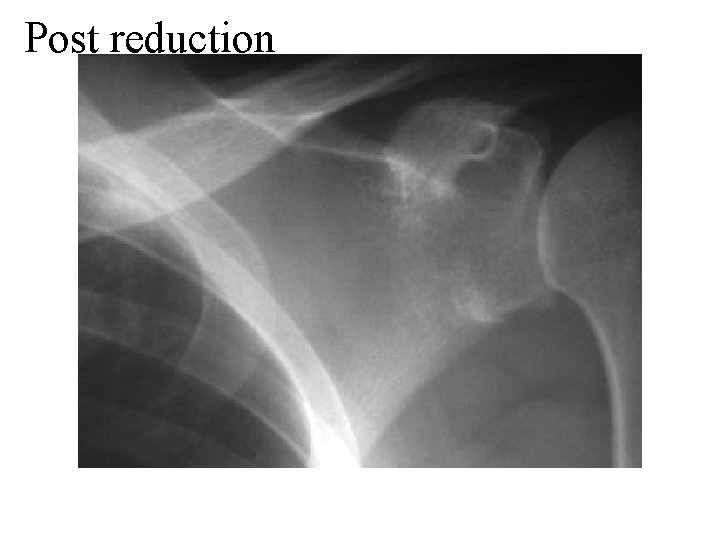

Post reduction:

Post reduction